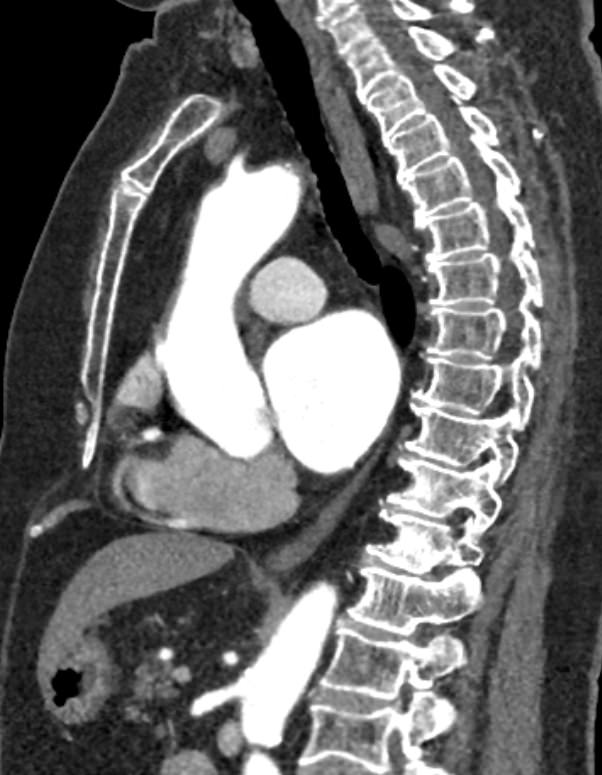

Грудная аорта делится на несколько отделов – восходящий отдел аорты, дуга аорты и нисходящий отдел. Корень аорты отходит непосредственно от левого желудочка, в его состав входят синусы Вальсальвы от которых берут начало коронарные артерии. После корня, прослеживается тубулярная часть восходящего отдела аорты, которая переходит в дугу аорты.

Дуга аорты дает начало брахиоцефальным артериям, которые питают головной мозг и верхние конечности. Затем следует нисходящий отдел аорты, распространяющийся через отверстие в диафрагме. От грудного отдела аорты отходят висцеральные артерии, кровоснабжающие органы средостения: бронхиальные, пищеводные, перикардиальные, медиастинальные артерии.

При истончении стенки аорты или ее ветвей формируется аневризматическое расширение участка сосуда, которое долгое время может никак себя не проявлять. Симптомы часто появляются при развитии осложнений – расслоения аневризмы (при разрыве внутренней оболочки сосуда и возникновения внутристеночной гематомы), разрыве аневризмы. Эти угрожающие жизни состояния можно избежать при своевременном выявлении аневризмы и проведения хирургического лечения.

Одним из информативных методов диагностики сосудистой патологии является мультиспиральная компьютерная томография грудной аорты и ее ветвей (КТ-ангиография). Метод сканирования при помощи рентгеновских лучей и цифровой обработки данных позволяет получать послойные снимки сосудов и трехмерные реконструкции сосудистой системы в мельчайших подробностях.

Для того, чтобы качественно визуализировать сосудистую систему КТ-ангиография предусматривает в обязательном порядке применение контрастного усиления. Йодсодержащее контрастное вещество вводится пациенту внутривенно и, благодаря способности контраста поглощать рентгеновские лучи, ярко контрастирует сосудистую систему на фоне окружающих тканей.

КТ-ангиография позволяет диагностировать аневризмы аорты, сосудистые аномалии развития, воспалительные изменения стенок сосудов, пристеночные тромбы, сужения просвета сосудов за счет сдавления извне близлежащими опухолевыми образованиями.